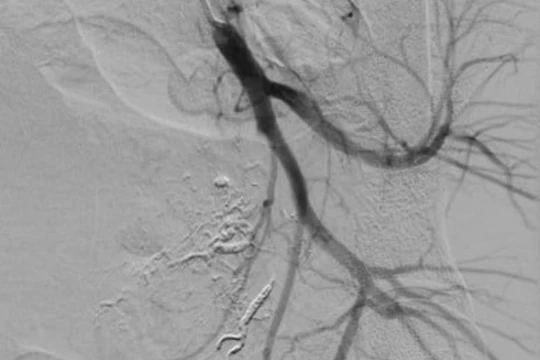

Hình ảnh sau nút mạch quanh động mạch trực tràng của bệnh nhân (Ảnh - BVCC)

90 phút “cân não” cứu sống sản phụ bị tổn thương động mạch trực tràng lần đầu tiên xuất hiện ở VN

VietTimes – Các bác sĩ ở Trung tâm Điện quang, Bệnh viện Bạch Mai, vừa cứu sống sản phụ bị tổn thương động mạch trực tràng hiếm gặp lần đầu tiên xuất hiện tại Việt Nam.